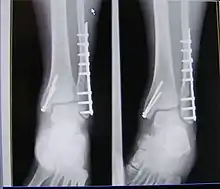

| X-ray of trimalleolar fracture repair before and after ORIF surgery | |

A trimalleolar fracture is a fracture of the ankle that involves the lateral malleolus, the medial malleolus, and the distal posterior aspect of the tibia, which can be termed the posterior malleolus. The trauma is sometimes accompanied by ligament damage and dislocation.[1]

Surgical repair using open reduction and internal fixation is generally required, and because there is no lateral restraint of the foot, the ankle cannot bear any weight while the bone knits. This typically takes six weeks in an otherwise healthy person, but can take as much as twelve weeks. Non-surgical treatment may sometimes be considered in cases where the patient has significant health problems or where the risk of surgery may be too great.[1]